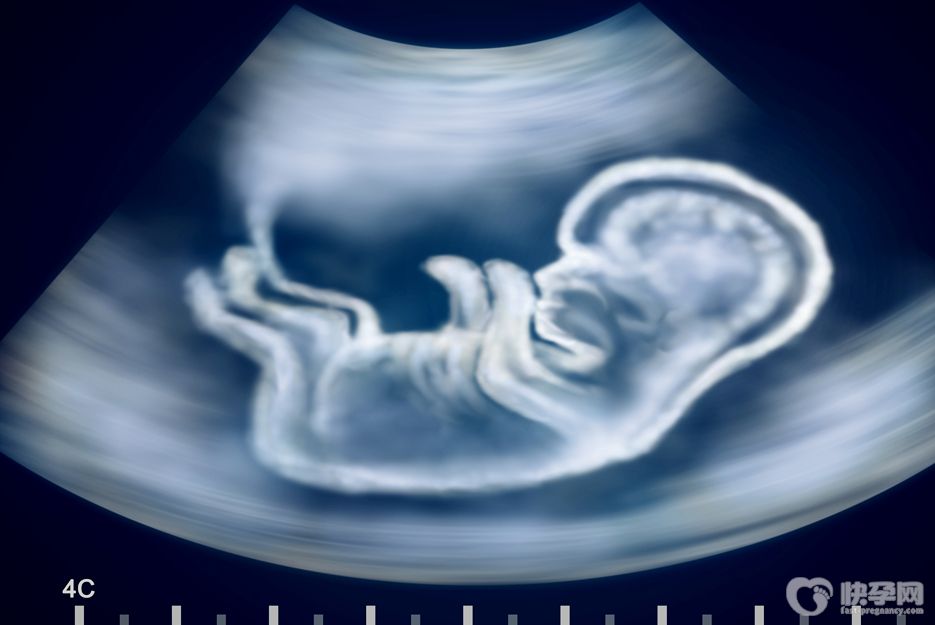

众所周知,移植新鲜胚胎的条件比较苛刻,稍不注意就容易导致失败。因此,生殖医生往往会选择将两个新鲜胚胎同时移植到子宫腔内。即使一个胚胎不能正常着床,另一个胚胎也可能发育成功,其成功率可达60%左右。

但是胚胎植入的成功率比较低,因为胚胎植入的生长会受到体内激素和宫内环境的影响。而且大多数人虽然移植了两个新鲜胚胎,但是同时存活的概率很低,也就是最后可能只有一个胚胎成功植入。那么高龄、试管反复失败放几个新鲜胚胎好?这可不是你自己能决定的!

试管婴儿一次放置多少新鲜胚胎,需要医生根据放置的新鲜胚胎的等级和不孕妇女的年龄来决定。不孕妇女35岁以下的,移植的新鲜胚胎为卵裂期新鲜胚胎,可移植两个胚胎。如果选择优质的新鲜胚胎移植,可以移植一个胚胎,避免多胎妊娠。

因为单个新鲜胚胎移植形成一个胎儿,是优生的条件,也就是说一次只生一个孩子是优生的基础。如果女性年龄超过35岁,可以在卵裂期移植3个新鲜胚胎,因为这样的人类新鲜胚胎成功植入的概率会增高。

资料显示,移植一个新鲜胚胎的妊娠率略低于移植两个新鲜胚胎的成功率,但活产率相对较高。即单新鲜胚胎移植妊娠率为44.6%,双新鲜胚胎移植妊娠率为44.7%,活产率分别为34.9%和34.2%。所以,不是每个人都适合移植两个新鲜的胚胎。

一般来说,对于年龄较大,多次移植失败,或者新鲜胚胎质量一般的女性,为了提高妊娠率,在身体条件允许的情况下,可以移植两个新鲜胚胎。而对于有移植两个新鲜胚胎意向的女性,医生也会综合考虑。